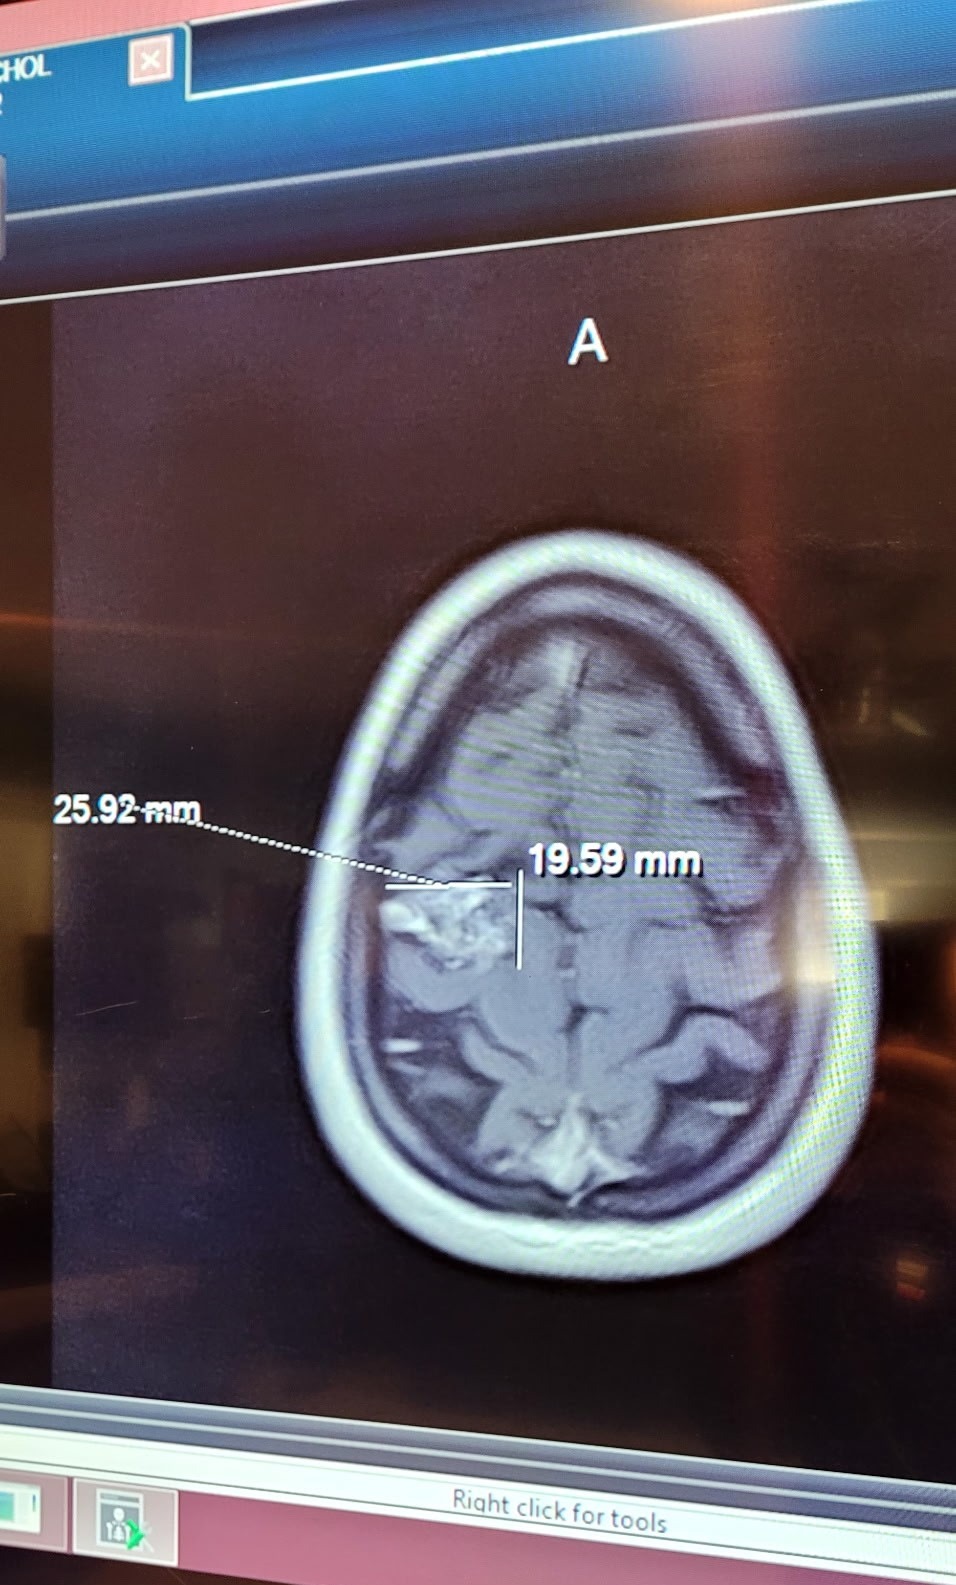

Earlier this year, our world turned upside down when Stephanie was diagnosed with a serious arteriovenous malformation (AVM) in her brain—a rare tangle of blood vessels that requires urgent treatment to prevent complications like bleeding or seizures. As a devoted wife, mom to their amazing kids—a 17-year-old who's navigating high school and a spirited 6-year-old full of energy—and the heart of their tight-knit family, Stephanie's strength has been nothing short of inspiring. But this fight has brought challenges we never saw coming, and we're turning to this community for a lifeline.